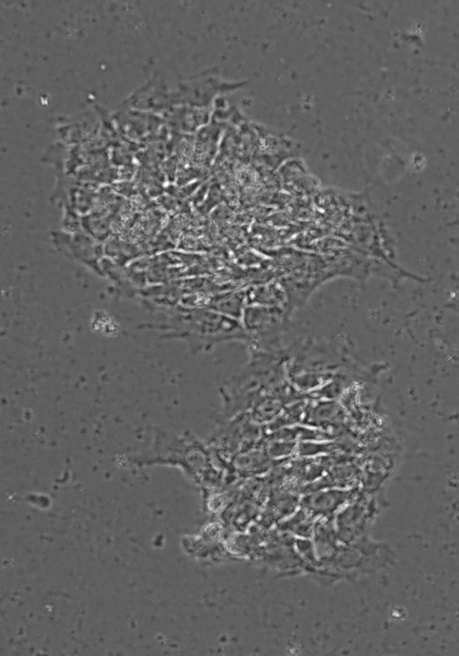

W Polsce komórkami iPS zajmuje się kilka zespołów. Badacze z Zakładu Biotechnologii Medycznej Wydziału Biochemii, Biofizyki i Biotechnologii UJ, pracujący pod kierunkiem prof. Józefa Dulaka i prof. Alicji Józkowicz, jako pierwsi opublikowali właśnie w czasopiśmie "Scientific Reports" pracę opisującą możliwość wykorzystania komórek iPS myszy i ludzi do badania mechanizmów cukrzycy.

Uzyskanie ludzkich iPS od osób cierpiących na jeden z rodzajów tej choroby było możliwe dzięki współpracy z Katedrą i Kliniką Chorób Metabolicznych UJ. Otrzymane mysie i ludzkie komórki iPS badacze zróżnicowali do komórek śródbłonka naczyń krwionośnych oraz komórek produkujących insulinę i glukagon – hormony trzustki.